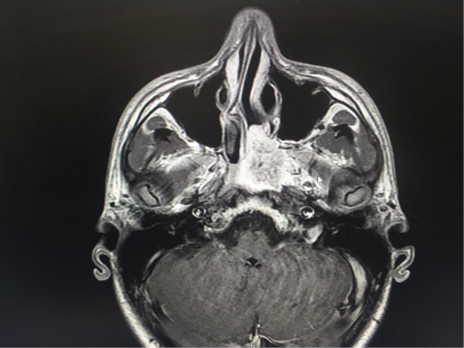

Resonancia Magnética Nuclear de senos paranasales contrastada con hallazgos masa hipointensa en secuencias T1 que realza ávidamente con la aplicación del medio de contraste de 38 x 35 mm que presenta señal de vacío en su interior, ubicado en la coana izquierda, infiltra el seno esfenoidal, el musculo pterigoideo interno, el tejido adenoideo a la altura del cavum faríngeo y erosiona la apófisis pterigoides ipsilateral. (Figura 3).